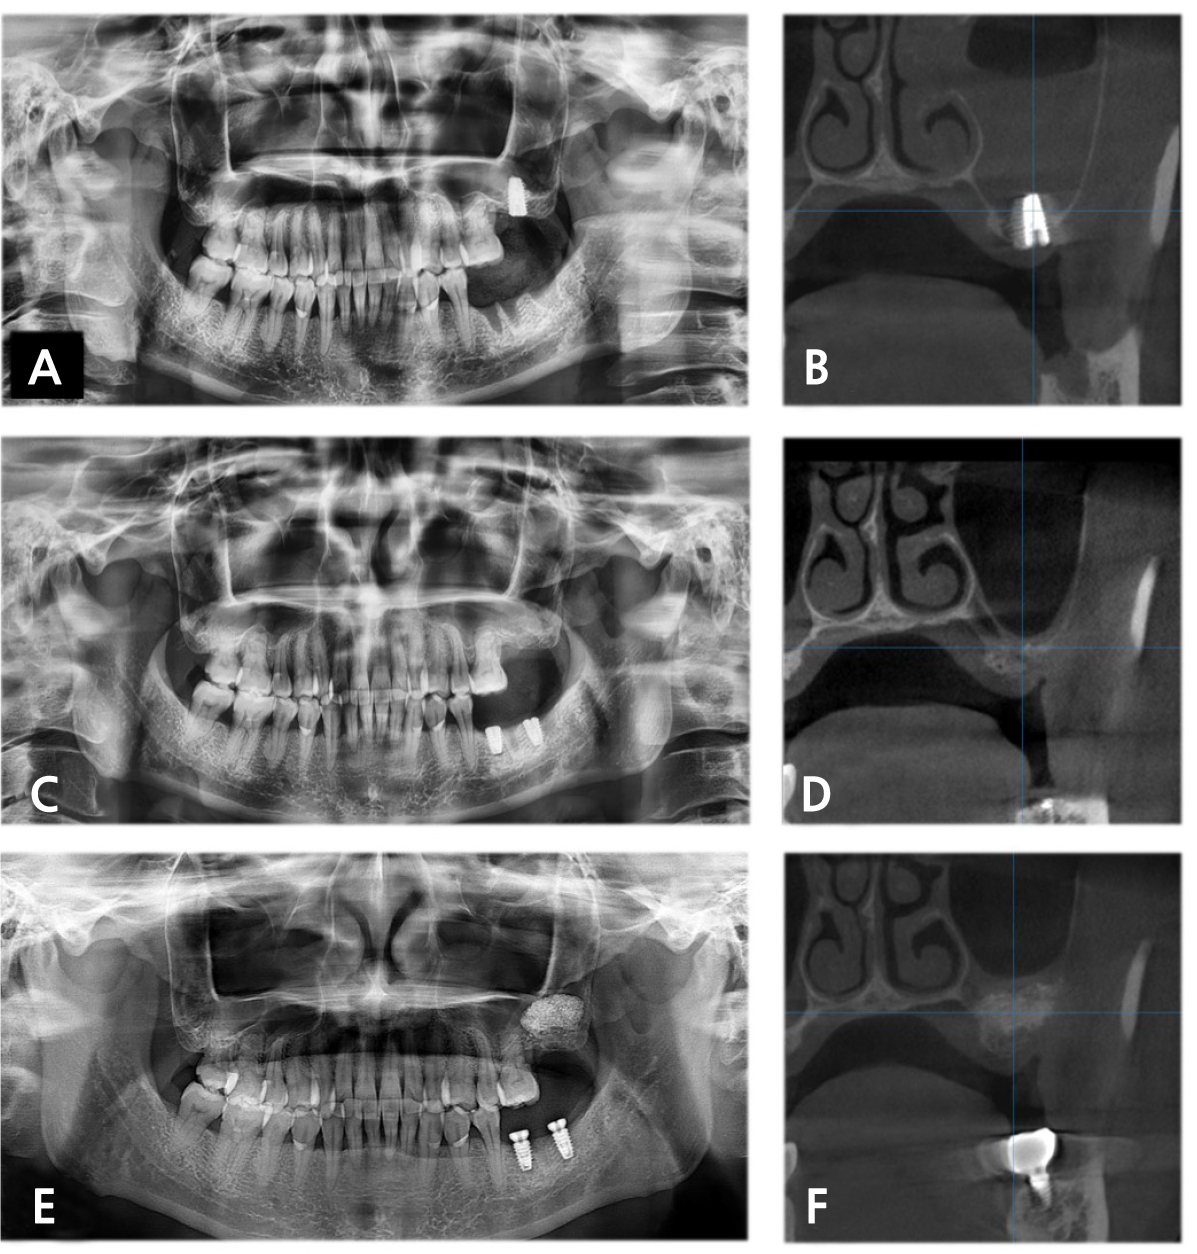

A 41-year-old female (patient 3) was referred to the Department of Oral and Maxillofacial Surgery to evaluate acute maxillary sinusitis after bone-added osteotome sinus floor elevation with simultaneous dental implant placement on the left maxillary 2nd molar. The patient complained about purulent nasal discharge and pain in the left midfacial area. Radiographic examination revealed no remarkable migration of graft material but opacification exceeding 50% of antral volume on the left maxillary sinus (Fig. 3A and 3B). The dental implant fixture was immediately removed, and nasal decongestants were prescribed. Three months after the fixture removal, the intact mucosal lining of the maxillary sinus was observed (Fig. 3C and 3D), and SALW was performed with bone substitute (Fig. 3E and 3F). The dental implant was replaced on the left maxillary 2nd molar four months after SALW, and the definitive prosthesis was delivered and surveilled for nine months.

Fig. 3.

In the 1st attempt at dental implant placement in patient 3. (A) Immediately postoperative PAN revealed suspicious perforation of the sinus floor and Schneiderian membrane. One week after 1st attempt, (B) CBCT showed opacification exceeding half of the antral volume in the left maxillary sinus. Three months after removing the fixture, (C) PAN and (D) CBCT showed intact mucosal lining of the maxillary sinus. Four months after SALW, (E) PAN and (F) CBCT demonstrated no remarkable opacification.